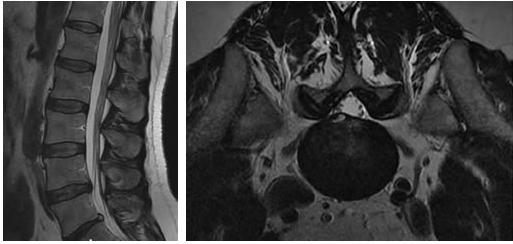

L’ernia discale è una patologia abbastanza frequente che interessa la fascia di età tra i 30 e i 50 anni; la sede più frequente è quella lombare. È determinata dalla rottura focale dell’anulus fibrosus che “contiene” il nucleo polposo che solitamente fuoriesce in sede posteriore o laterale. Poiché importanti revisioni casistiche hanno dimostrato che anche i risultati a distanza del trattamento chirurgico non sono scevri da conseguenze, negli ultimi anni tali indicazioni si sono molto ristrette, essendo fondamentalmente riservate ai casi in cui sono presenti paresi/paralisi nervose o sindrome della cauda. Nel contempo sono state messe a punto altre terapie “mini-invasive” che con accesso percutaneo tendono a “ridurre” il volume discale o a “cicatrizzare” l’anulus fibrosus.

Il trattamento che noi pratichiamo prevede l’erogazione di radiofrequenza pulsata (RFP) e l’iniezione di cortisonico a lento rilascio. Con guida TC viene posizionato con accesso postero-laterale (per la sede toracica e lombare) o antero-laterale (per la sede cervicale) un ago da 22G (0,6mm) in prossimità del forame di coniugazione corrispondente; in questo ago, previa estrazione del mandrino, si inserisce coassialmente l’agoelettrodo; successivamente si posiziona sulla cute una piastra dispersiva per chiudere il circuito con il generatore di radiofrequenza. Si eroga quindi, previa stimolazione a 50 Hz, radiofrequenza pulsata a 2 Hz per sei/dieci minuti che consente di neuromodulare il ganglio della radice interessata. L'utilizzo della RFP consente di agire solo sulle fibre nocicettive del ganglio (evitando di ledere quelle motorie e sensitive) poiché alla punta dell'agoelettrodo, posizionata a qualche millimetro dal ganglio, si raggiunge una temperatura massima di 42° C. Sempre attraverso lo stesso ago, dopo aver estratto l’agoelettrodo, si iniettano 2-4 ml di steroide a lento rilascio. Dopo qualche minuto si asporta l’ago, si medica il piccolo foro cutaneo di ingresso, si appone un cerotto medicato e si toglie la piastra dispersiva. Il paziente viene tenuto in osservazione per 1-2 ore e poi riprende le sue normali attività.